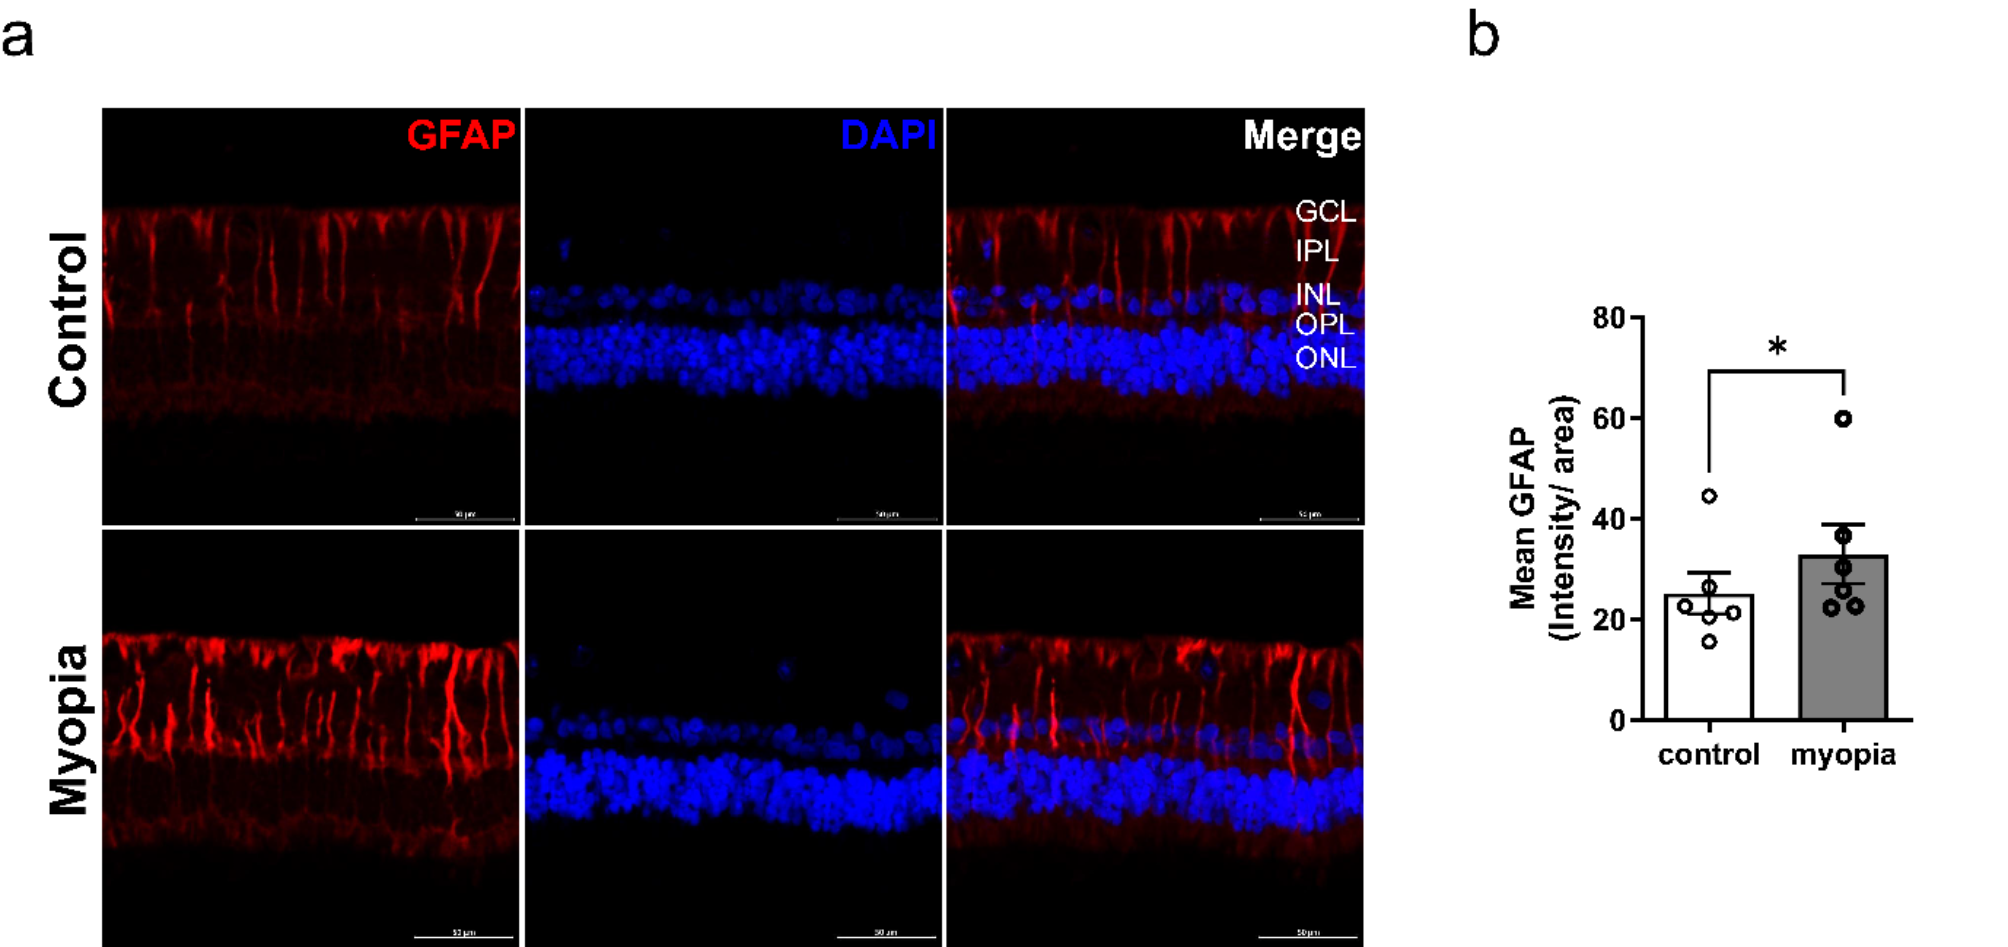

Fig. 3

Identification of reactive gliosis in Müller cells via glial fibrillary acidic protein (GFAP) immunohistochemistry of the myopic retina. (a) GFAP expression increased in Müller cells of the myopic retina compared to that of control retina. (b) Quantitative analysis showed a significant increase in mean GFAP immunofluorescence intensity in the retina of myopic rabbits compared to controls.